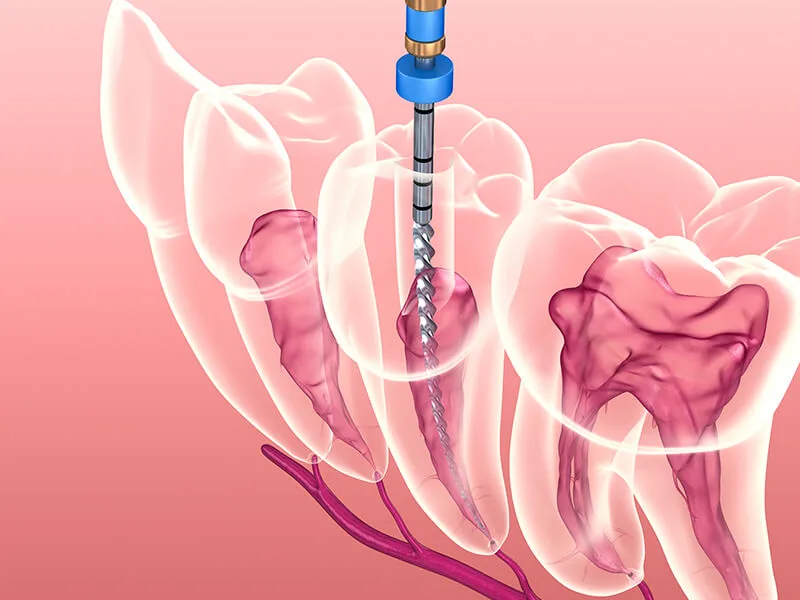

Além de tratar infecções e inflamações, a unidade utiliza recursos técnicos modernos para fundamentar resultados precisos. O suporte de profissionais capacitados e o uso de microscopia e sistemas rotatórios elevam a segurança e a eficácia das intervenções.

Tratamento de Canal: Remoção da polpa inflamada com total precisão técnica;